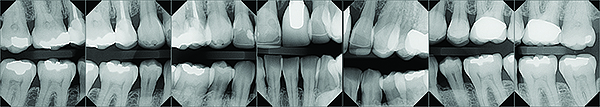

A series of full-mouth diagnostic radiographs that visualize each tooth or implant are critical as a baseline (Figure 11). The frequency and type of radiographs needed at maintenance depends on the severity of periodontal disease, as well as the extent of restorative treatment and caries susceptibility. With more advanced periodontal disease and restorative concerns, more frequent radiographs may be indicated. Vertical bitewing radiographs provide a better view of osseous crest levels and should be considered over horizontal bitewing radiographs for periodontal cases (Figure 12).

Fig 11. Full-mouth series of radiographs.

Figure 11